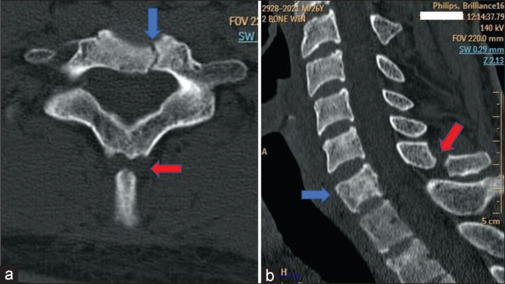

Results: Despatch from greater-than-ideal height (>7 m) and speed (>5 knots) causes a high-velocity impact of the body with water in a non-aerodynamic configuration, exposing maximal body area at penetration. The brunt is borne by the torso/back, specifically, the lungs, ribs, and posterior aspect of the spine. The injuries result from direct trauma, sudden deceleration, barotrauma, and hyperflexion. Computerized tomography (CT) is the imaging of choice in the assessment of these injuries. Prompt evacuation to an equipped center, whilst stabilizing the spine in the suspected, proves pivotal to the outcome.

Conclusions: Adverse slamming dynamics cause accidental injuries in helocasting. Thorax and spine are predominantly traumatized, both directly and indirectly, and are assessed best using CT. Timely spine stabilization and evacuation prove vital. Accurate assessment of height/speed and adherence to their ideal limits, at despatch, may avert such injuries.